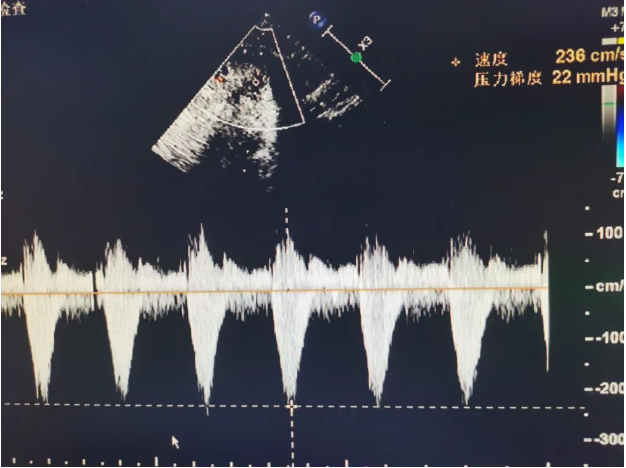

PW:主动脉瓣流速156cm/s,降主动脉流速236cm/s